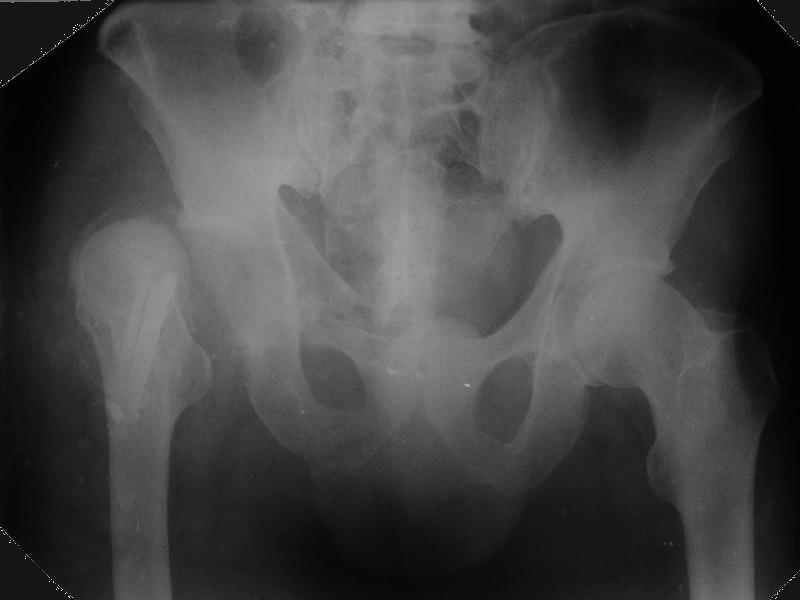

Уважаемые коллеги,Мужчина 1952 г.р. поступил в 36 больницу Екатеринбурга 1 июня 2004 г. Диагноз: Множественный перелом ребер слева, субтотальный гемоторакс, оскольчатый перелом шейки правого бедра.Повреждение таза не диагностировано. 17 июня 2004 г. - открытый остеосинтеза шейки бедра винтами с костной аутопластикой. Заживление раны первичное. Выписан 1 июля. 4 июля отметил укорочение конечности. При контрольном осмотре через 1 месяц после остеосинтеза - передний вывих бедра. Неправильно срастающийся перелом костей таза.Вопрос - особенности эндопртезирования тазобедренного сустава в этой ситуации?

Перелом там от бокового сжания, похоже на LC-I, т.е. компрессионный перелом крестца и на этой же стороне лонной и седалищной. Впадина выглядит совершенно целой. Если там и есть какая-то импрессия в переднем отделе - то микроскопическая.

По видимому снимки н/к сделаны в положении наружной ротации 90гр. И если даже так, то можно определить, что после выполненного остеосинтеза, шейка бедра практически отсутствует.